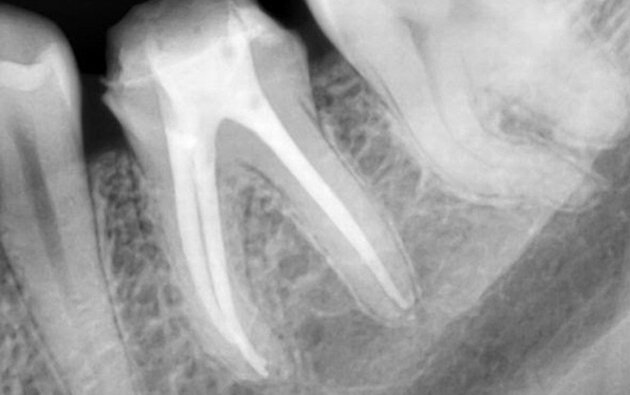

3 корневых канала плотно запломбированы